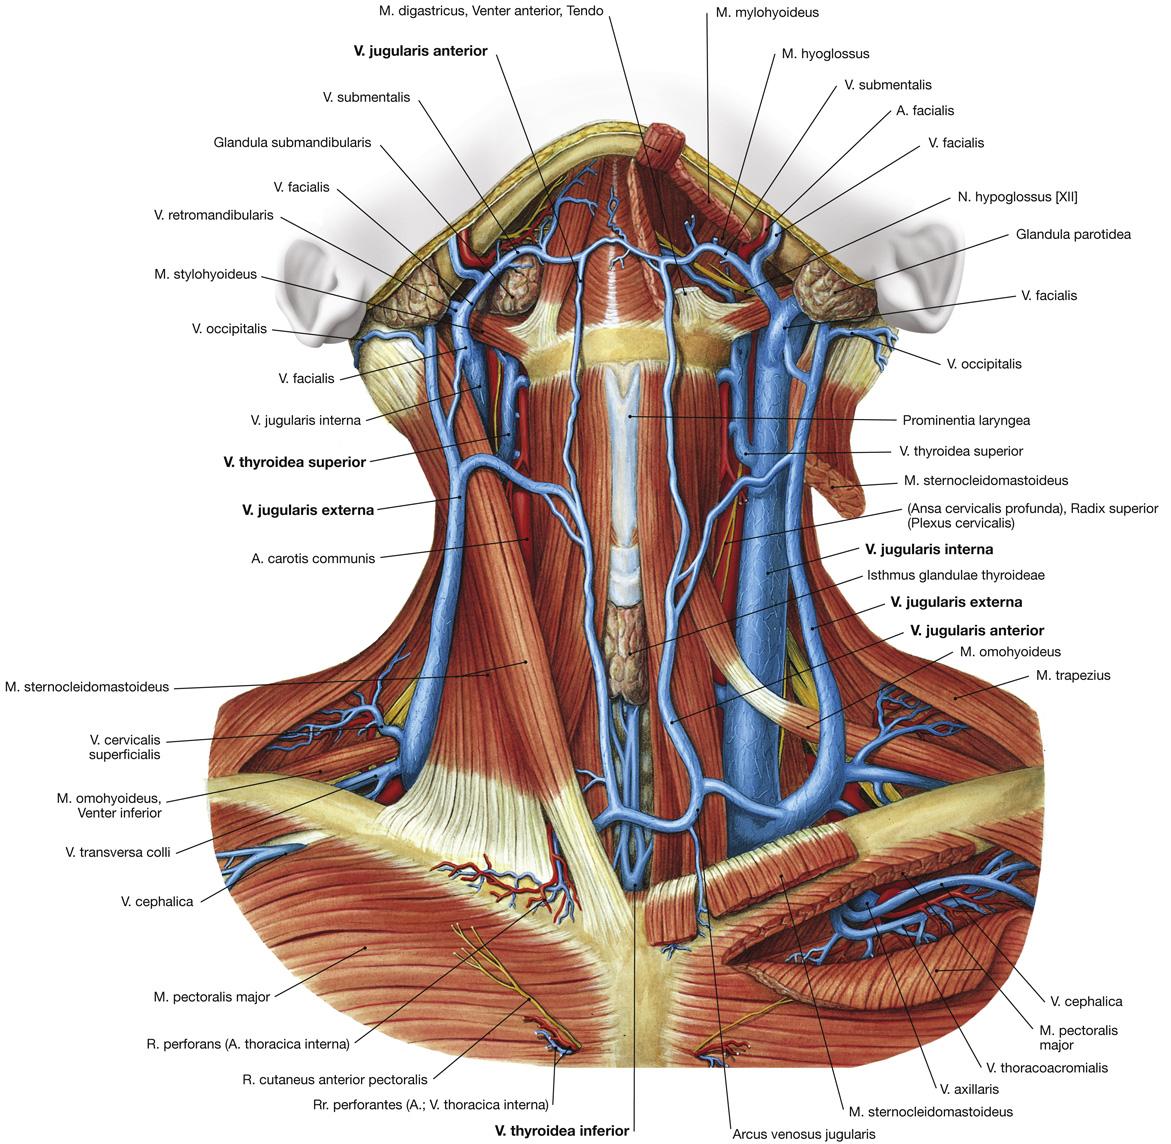

Fig 3.32: v. jugularis interna en externa

processus mastoideus m sternocleidomastoideus -

v brachiocephalica

v subclavia -

v jugularis interna

-

v jugularis externa

bron: v retromandibularis over m sternocleidomastoideus uitmonding: heel variabel

-

v jugularis anterior

|

Sobotta: Fig 11.89